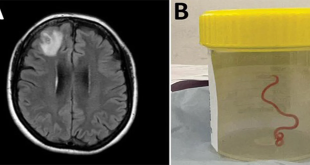

المزيدفي أول حالة من نوعها…أطباء أستراليون يستخرجون دودة طفيلية من دماغ امرأة

سيدني-سانا أعلن أطباء أستراليون اليوم أن دودة طفيلية دائرية تكون موجودة عادة لدى الثعابين